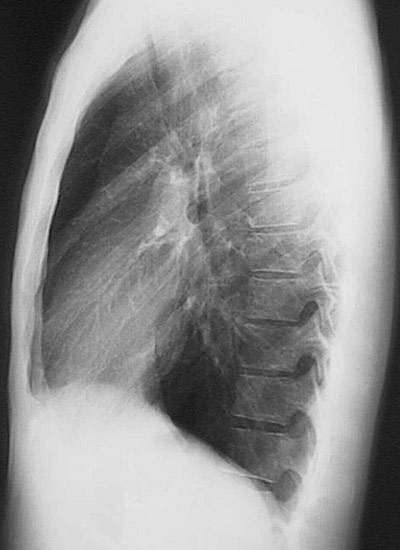

The lateral chest radiograph seen here demonstrates a normal appearance to the lung fields and heart shadow in a tall, thin adult male.